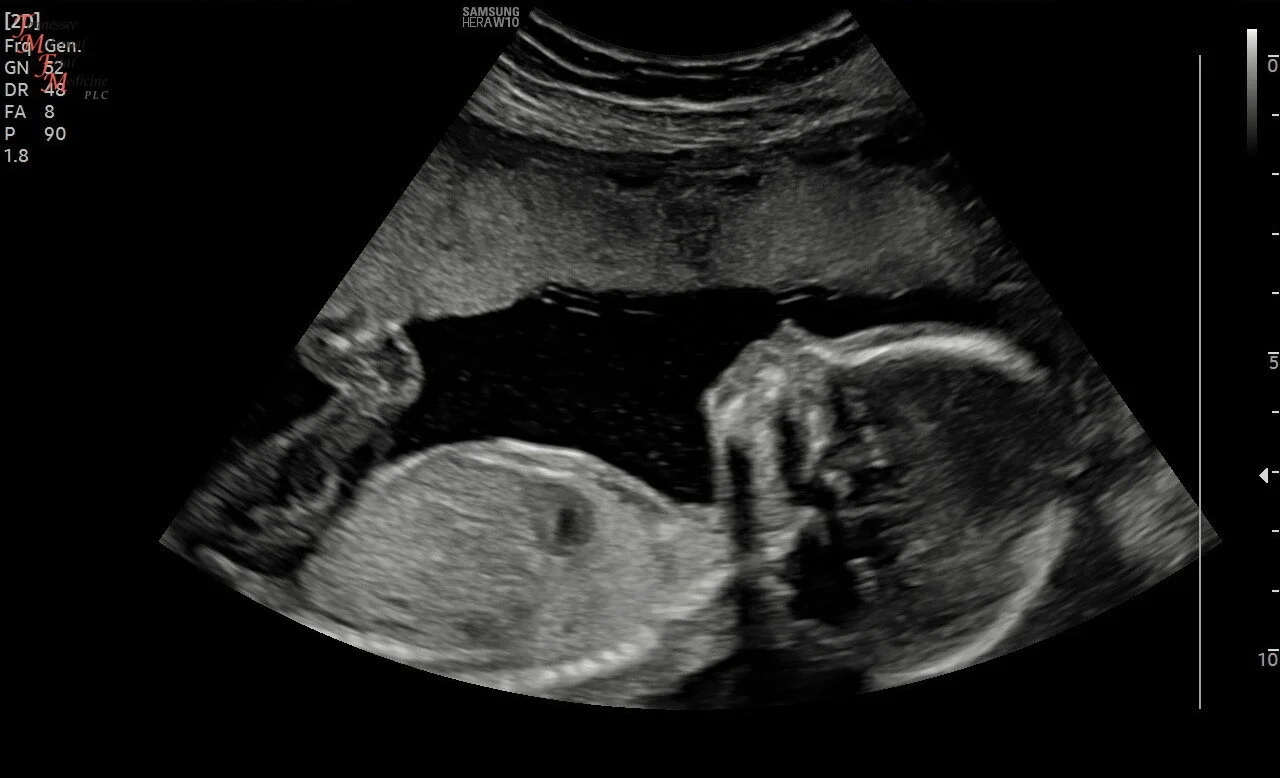

The dark, crescent-shaped figure below the baby is my subchorionic hemorrhage the day they found it on the ultrasound.

So what was the explanation for my bleeding? They couldn’t find an answer that night. They sent me home later with discharge papers that read, “Threatened miscarriage” and instructed me that if my bleeding persisted or got worse or I passed clots—I would know what was happening. There were no guarantees. No answers. Simply a “wait to see what happens” response from the ER doctor. We drove home again in silence. I could feel the fear welling up inside me faster than I could breathe almost. I had to just wait? Just wait and see if she came out over the following few days? How could I sleep? How could I walk to the bathroom to pee without fearing my baby might pass right into the toilet? How could I be a mother to my other baby boys with this gripping, paralyzing fear taking over me? The next day, I wanted a second opinion. I scheduled an ultrasound at a third party place in town with an ultrasound tech who specialized in high risk pregnancies. I told her everything that had happened the night before and she calmly said, “I think I know what’s happening Kelsey and if I’m right—you’re going to find hope that things might turn out okay…” Caleb and I held our breath again as she turned on the screen. Moments later she said, “I was right. Look right here”, as she pointed at the screen at a large dark shape underneath the sac where my baby was. “This dark space here is called a subchorionic hemorrhage, and this is the source of your bleeding.” A subchorionic hemorrhage? What on earth was that? Does it go away? Is it going to kill my baby? A million questions racing through my mind. She explained to me that she actually sees this type of thing pretty often but that mine in particular was bigger than most. She explained that smaller ones almost always dissolve over time and don’t generally cause issues or pose risks to the baby but that my bleed was bigger than she’d like it to be. She told me she had high hopes that it would slowly resolve on its own but that I needed to be careful. Not lift anything. Take it easy for the next several weeks. She explained that I would continue to bleed—probably everyday for the next unforeseeable future because of the sheer size of the hemorrhage that would continue to slowly come out. But she told us to have hope. To trust God. And to have faith that baby girl would be okay. We left there feeling an ounce of hope we didn’t have the night before. And for that—we were grateful. But we were still ridden with fear that at any moment, things could change and we could still lose her. We couldn’t believe it—but she was still alive.